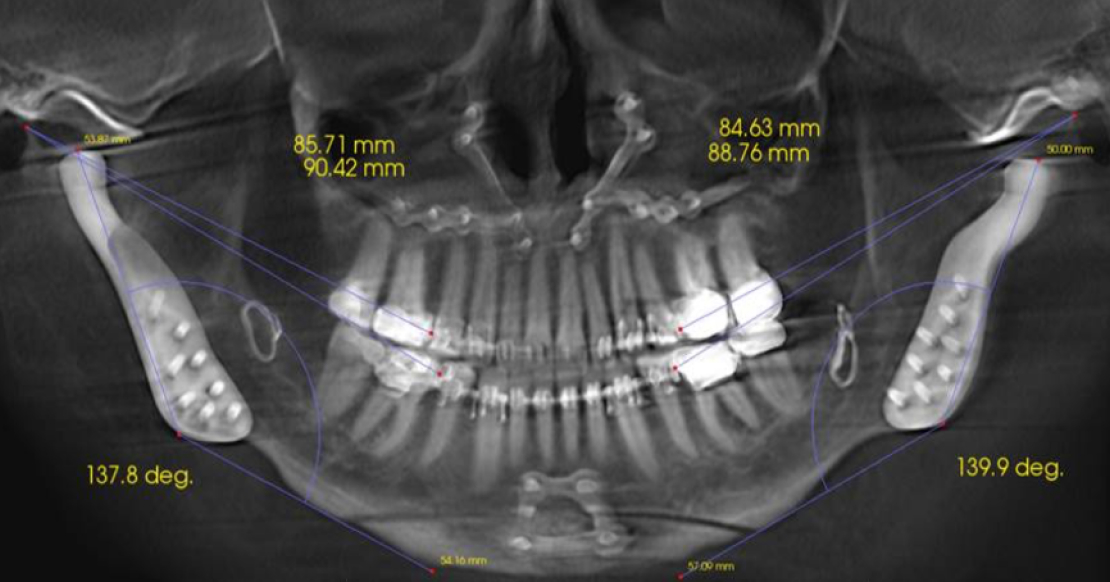

Patients presenting with a Class II occlusion can also be challenging to restore, because of the lack of anterior tooth contact. Depending on the extent of the Class II relationship, these plans require more extensive intervention; they may necessitate orthodontic treatment, orthognathic surgery, or both (Fig. 4) to correct the skeletal relationship before predictable restorative treatment can begin.

Early recognition and intervention are ideal to ensure adequate growth. The window to stimulate growth has often been missed in the adult population, so restorative, orthodontic, or orthognathic interventions may be needed to correct the occlusion and

esthetics. Stability in the system is imperative for the long-term success of the treatment.